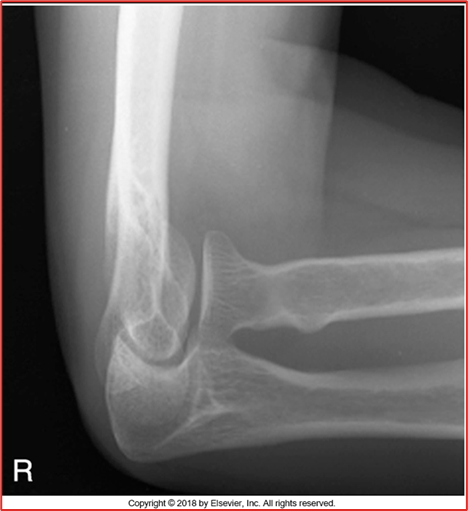

acute flexion

these 2 images of the elbow are in what position (2 for 1!) CR perpendicular to humerus and then CR perpendicular to forearm

distal humerus

this acute flexion of the elbow image is showing the __ __